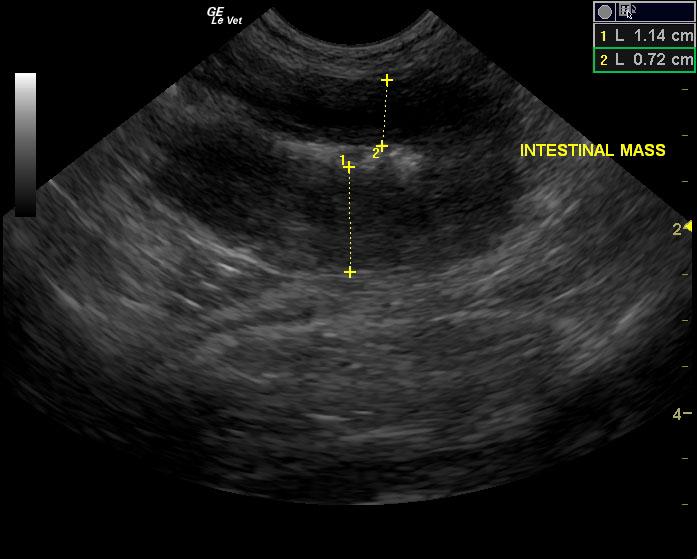

A seven-year-old MN DSH cat was presented with lethargy with the owner reporting that the cat’s behavior and temperament had changed. On urinalysis the urine was straw in color and clear; USPG was inappropriate (1.021), hematuria was present. The urine protein/creatinine ratio was 1.1. Abnormalities on CBC and serum chemistry were anemia, neutrophilia, lymphopenia, monocytosis, hypoproteinemia, and azotemia. Abdominal radiographs revealed an left nephromegaly and a mass effect in the gastrointestinal tract.